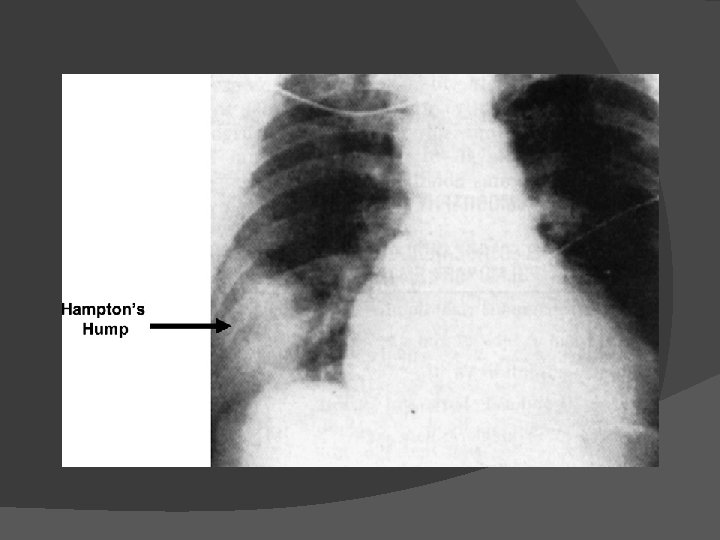

Angiografia pulmonar

Conventional pulmonary angiogram of the right lung with intraluminal filling defects in the lobar artery and segmental and subsegmental arteries of the lower lobe. Kearon C CMAJ 2003; 168: 183 -194 © 2003 by Canadian Medical Association

Kearon C CMAJ 2003; 168: 183 -194 © 2003 by Canadian Medical Association